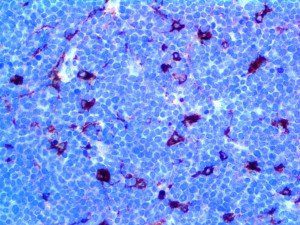

It is the ICU physician who is most likely to witness one of the deadliest manifestations of the abnormal immunological response, the cytokine storm syndrome (CSS). This response is also referred to by some as the cytokine release syndrome (CRS). CSS is characterized by continuous activation and expansion of macrophage and lymphocyte populations, which secrete large amounts of cytokines, causing the cytokine storm. This massive cytokine release is akin to hemophagocytic lymphohistiocytosis (HLH) disease, a syndrome characterized by initial unchecked and persistent activation of cytotoxic T lymphocytes and NK cells.

Clinical and laboratory manifestations of HLH include fever, enlarged liver and/or spleen, neurologic dysfunction, coagulopathy, liver dysfunction, cytopenias (i.e., low levels of erythrocytes, leukocytes, and/or platelets), hypertriglyceridemia, hyperferritinemia, hemophagocytosis, and eventually diminished NK cell activity as the immune system becomes progressively paralyzed. HLH can be familial (primary HLH) or secondary to another disease process (sHLH), such as rheumatic disease, in which it is referred to as macrophage activation syndrome (MAS, characterized by elevated ferritin).